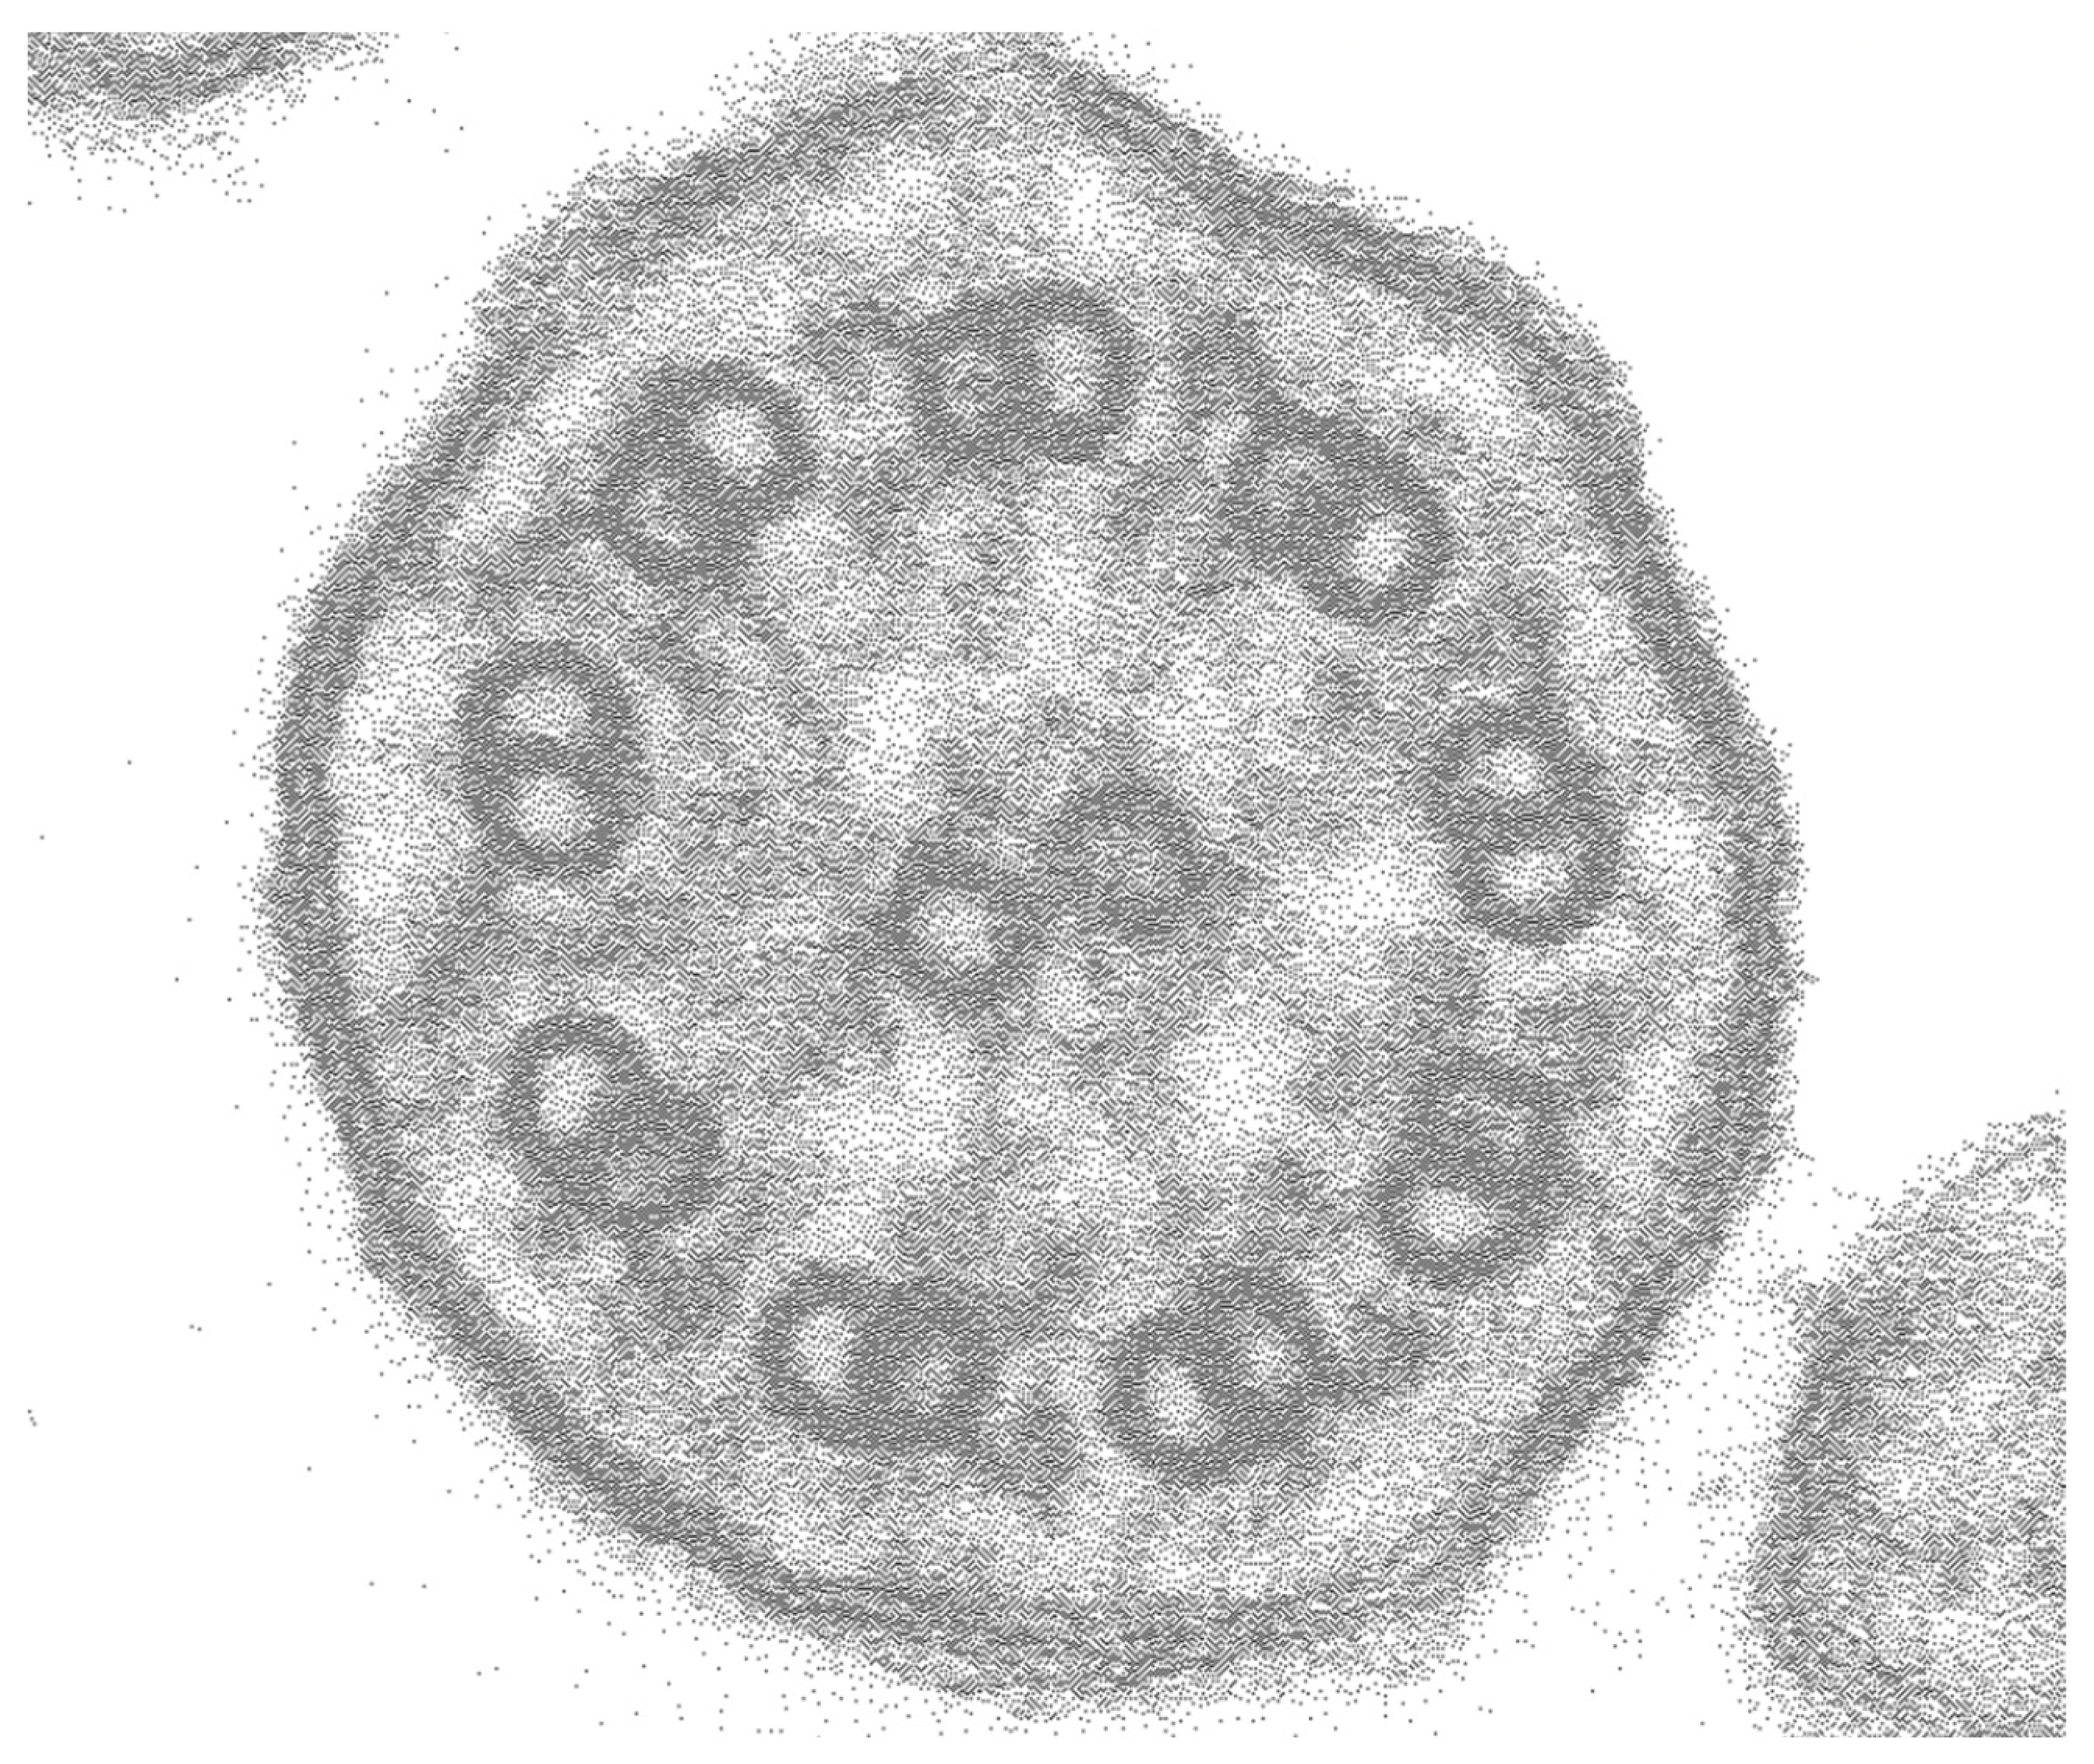

2. Case Presentation